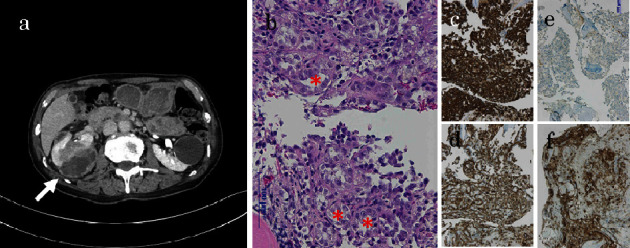

We encountered a case of metastatic renal cell carcinoma in which the serum level of KL-6, a therapeutic marker, was exceptionally high and fluctuated with the progression of treatment. A 74-year-old man was diagnosed with right renal cystic cancer and multiple metastases in October 2022. The KL-6 level was 27490 U/mL. He started treatment with lenvatinib and pembrolizumab. KL-6 decreased to 3885 U/mg in February 2023. The patient's proteinuria worsened, leading to the discontinuation of lenvatinib. KL-6 increased to 25950 U/mL in April. He discontinued pembrolizumab and started taking cabozantinib. In September, drug-induced bilateral inflammatory pneumonitis developed. He discontinued cabozantinb and began taking axitinib. KL-6 decreased; however, he suffered from severe diarrhea and subsequent renal insufficiency. He discontinued axitinib in November. KL-6 increased to 29640 U/mL in December.